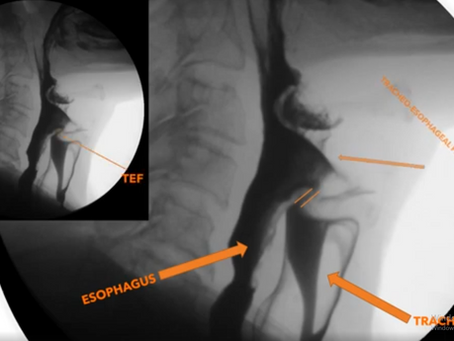

English Text:Tracheoesophageal Fistula (TEF) and Oral Contrast Esophagography Türkçe Metin:Trakeoözofageal Fistül (TÖF) ve Oral Kontrast Özefagografi

🔘 Türkçe versiyona gitmek için aşağıya kaydırın 🔘 Scroll down for English version English Text:  Tracheoesophageal Fistula (TEF) and...